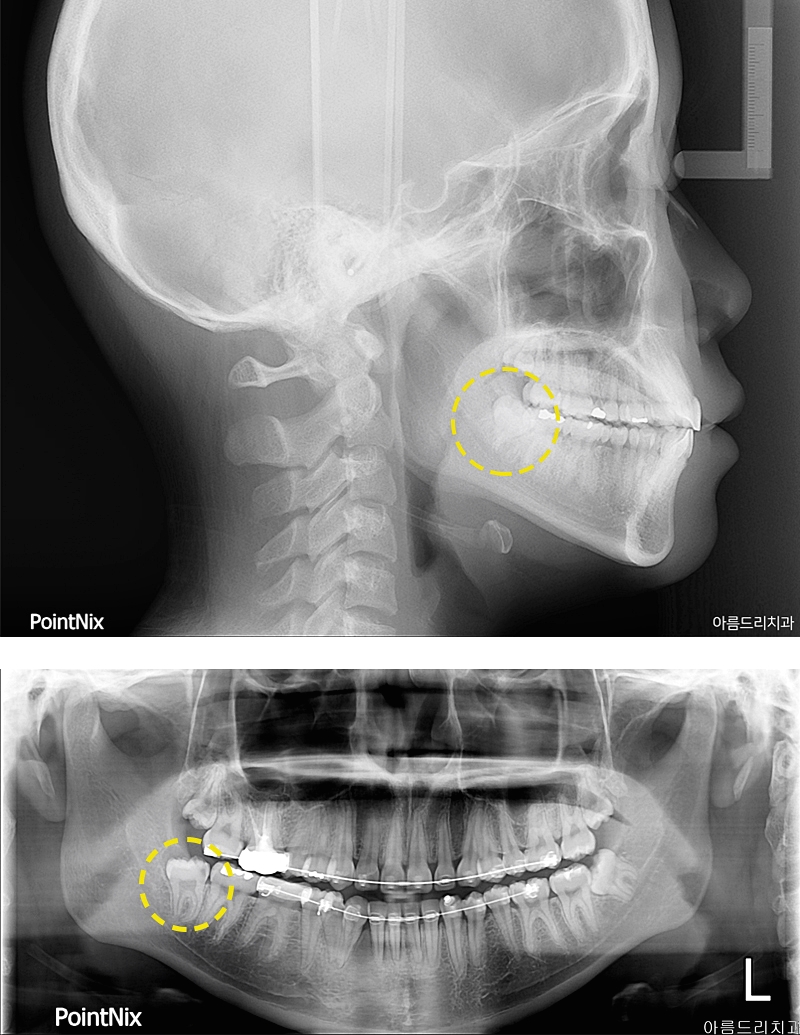

환자분의 엑스레이를 확인해본 결과 사랑니 자체가 다 자랐지만 잇몸에 매복되어 구강내에서 직접 눈으로 볼 때는 잘 보이지 않고 앞부분만 살짝 보이기 때문에 이제 사랑니가 나는 것인가? 하는 생각을 하실 수 있겠는데요. 엑스레이를 찍어본 결과 잇몸안에서 사랑니가 이미 다 난 상태이며 어금니쪽의 머리 부분과 뿌리부분에도 서로 맞닿아 있어 통증을 느낀다고 하셨었어요. 보통 사랑니의 경우 사춘기가 지나고 사랑을 알기 시작할 때 나온다고 해서 사랑니라는 이름이 생겼다고 해요. 생기게 된 원인은 사회가 발전하면서 생기는 식습관에 변화에서 찾을 수 있다고 했었어요. 질긴 음식을 먹던 예전에 비해서 점점 부드럽고 정제된 음식을 섭취하는 문화가 자리잡게 되어 음식을 찢고 씹어야 하는 저작 기능을 담당했던 치아의 역할이 줄어들면서 치아가 퇴화하고 아래턱의 크기가 감소하게 되었었어요. 식습관의 변화로 사랑니가 자리잡을 공간이 부족이 부족하게 된 것이 원인이었어요. 또 다른 이름으로는 가장 늦게 나오는 치아라고 해서 정확하게는 제3대구치고 불리는데 원래 정상적으로 나온다고 하면 어금니와 같은 역할을 하게 된다고 해요. 하지만 현재는 그렇지 않다는 것 이었어요.

사랑니의 발치를 권하는 이유는 입 안 가장 안쪽에 위치하여 칫솔이 닿지 않는 구조 때문에 충치가 쉽게 발생하기도 하여서 옆치아에 충치를 유발하거나 잇몸에 염증일 유발할 가능성이 높기 때문이었어요. 턱관절의 자리가 부족한 경우에는 사랑니 자체가 바르게 나지 않아 다른 치아들을 밀면서 신경통을 유발할 가능성이 높기도 해요. 사랑니 중에서도 매복사랑니의 경우에는 잇몸 안에 숨어서 자라는 사랑니를 말하는 것이에요. 잇몸에 부분적으로 매복되어 일부만 밖으로 노출되어 있거나 사랑니 전체가 잇몸에 매박되어 CT촬영을 통해 발견되는 경우도 존재했어요. 구강에 통증이 있어 치과에 방문한 후 잇몸 속에 자리잡은 매복사랑니 때문에 놀라는 환자들도 많았어요. 진달을 받았다면 매복사랑니발치는 최대한 미루지 않고 진행하는 것이 좋아요. 일반적으로 치아의 머리부분에 해당하는 치관이 일부가 노출되어 있으며 나머지 부위는 잇몸에 덮여 보이지 않은 경우가 다수인데 이 경우 음식물찌거기나 이물질, 치태 등이 쉽게 쌓이기 쉬운 구조여서 충치 유발이 되고 양치만으로는 찌꺼기를 제거하기에 용이하지 않기 때문이에요. 그렇기에 매복사랑니발치를 하지 않고 방치할 경우 잇몸질환의 확률이 높아지며 어금니의 뿌리 손상, 인접 치아 뿌리, 턱뼈에 압력을 가한 통증을 유발하여 삶의 질을 저하시킬 수 있어요.

염증 유발인자들이 쌓이고 치아 주변에 계속해서 위치할 경우 급성적으로 잇몸 염증이 발생할 수 있는데 초기에는 약간의 붓기와 양치질 중에 보이는 출혈이 대표적인 증상이에요. 하지만 방치하게 되면 매복사랑니통증이 증가하여 악취를 동반하는 치주염으로도 발전하게 될 수 있었어요. 치주염이 더욱 진행될 경우 해당 치아 주변의 치조골 뿐 아니라 전방에 위치한 치아 주위 조직에도 염증이 진행될 수 있는 만큼 매복사랑니통증이 느껴진다면 서둘러 진료를 받고 염증관리와 발치를 진행하는 게 중요한 부분이었어요. 하지만 치료가 쉬운 일만은 아니에요. 사랑니는 뿌리가 아래 턱의 신경과 근접해 잇는 경우가 많으며 신경 손상의 가능성이 있고 매복사랑니의 경우 치아 구조와 턱뼈의 위치 등을 고려해서 신중한 치료가 이루어져야 하기 때문이에요. 자칫 신경을 건드려 손상되면 마비의 위험까지 따르기도 해요. 그래서 매복사랑니발치 위험부담이 따른 치료이기도 해서 그만큼 더욱 신중한 의료기관 선정이 중요하기도 해요. 발치 치료가 시작되면 먼저 치근단 방사선 사진 및 CT영상 장비를 통해 치아의 상태 및 매복 모습, 기울기 등 전반적인 사항들을 파악하게 되었어요. 파악한 결과를 토대로 체계적인 치료 계획을 세우게 되어요. 발치 과정 중에 혈관이나 신경이 손상되면 감각 이상 증상이 생길 수 있으며 절개 부위의 봉합이 미숙할 경우 치유 자체가 지연되는 문제가 생길 수도 있으니 매복사랑니 발치를 고려 중이라면 꼭 임상경험이 풍부한 치과를 선택해야만 했어요.

마지막으로 환자분의 발치 후 모습을 확인해보실 수 있는데 우측(사진상으로는 좌측)에 해당하는 매복사랑니발치를 별다른 통증없이 치료를 완료하였으며 얼마 후에 좌측에 있는 사랑니도 주변치아에 문제가 될 수 있는 소지가 많아 추가적으로 발치를 진행했었어요. 환자분께서도 통증에 대한 우려를 많이 하셨는데, 진료를 마친 후에는 진작 치료를 받을 걸 그랬다는 말씀을 남겨주셨었어요. 참 그리고 앞으로 매복사랑니 발치를 고려하는 분들을 위해 발치 후 주의사항도 알려드릴께요. 치료 후에는 출혈 예방을 위해 거즈를 2시간 이상 잘 물고 있어야 하겠고요. 금연과 금주도 최소 2주 이상 삼가해야 하겠어요. 병변 부위를 혀로 건드리거나 손으로 만져서도 안되요. 냉찜질과 처방 받은 항생제를 잘 이용해 주어야 하며 사랑니와 빠진 부위에 건강한 잇몸이 찰 수 있도록 주의사항을 잘 지켜주셔요. 아파서 치과를 내원하기 보다는 정기적으로 검진과 스케일링을 하면서 문제가 발생하기 전 예방관리와 더불어 질환 발생 시에도 빠른 처리를 받으시길 권유드려요. 더 궁금한 점이 있다면 아름드리치과 카카오톡 채널을 통해 상담이 가능하며 전화 및 홈페이지 문의도 친절한 상담을 약속드리겠어요.